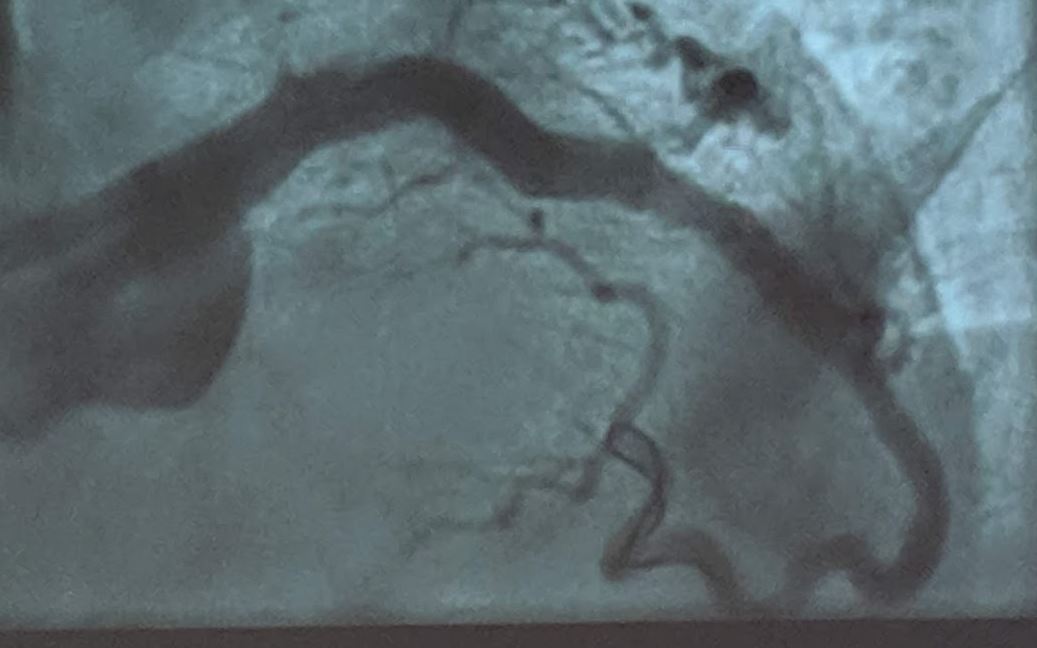

#RotaShock case by Dr. Shailendra Singh at Lehigh Valley Health Network (@LVHN). Patient presented with severe calcification of the RCA. After encountering a balloon uncrossable lesion, Dr. Singh used rotational atherectomy to facilitate passage of #IVUS. Encountering diffuse